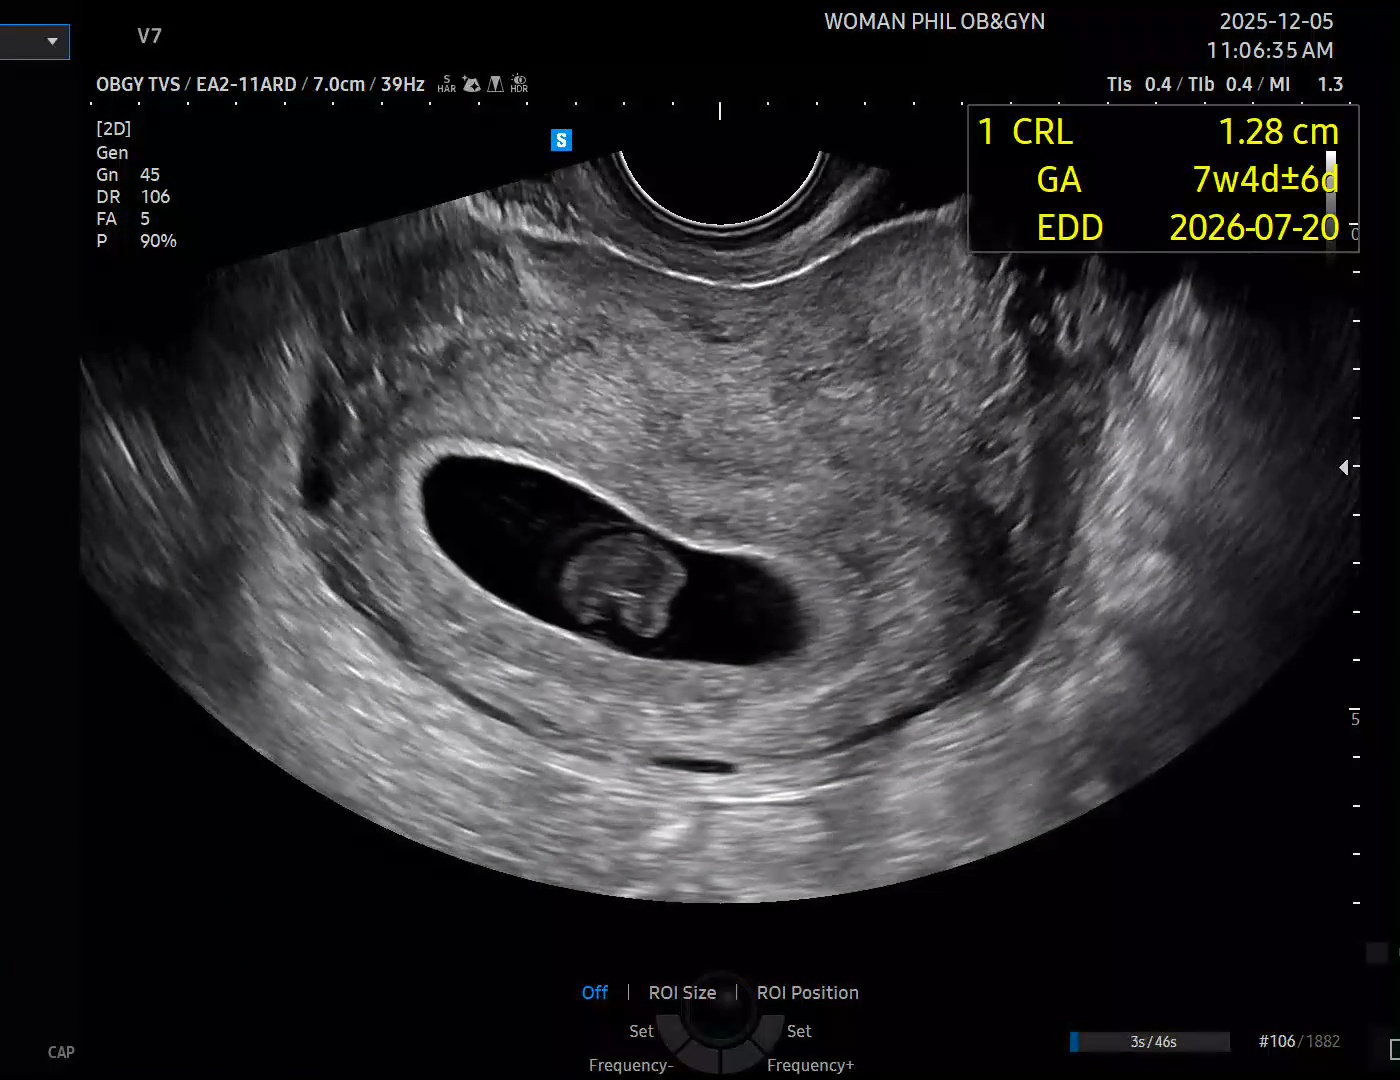

8주0일 계류유산이래요

오늘 초음파서 7주4일정도되는 크기고 아기의 형체도 흐릿하고 무엇보다 심장뛰는게 보이지않더라구요. 계류유산이라고 소파술하자시는데 가망없겠죠? 첫아이땐 입덧때문에 물도 제대로 못마셨는데 임신을 처음알고난 시점보다 점점갈수록 입덧도없는거같고 불편감이 좀 사라지는거같고 냄새만 예민한정도였네요..